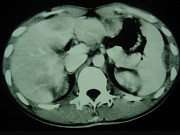

- 单项选择题男,35岁, 病人低热、消瘦、乏力,左右季肋区疼痛, CT扫描如图所示,请选择最佳诊断 ( )

A、肝海绵状血管瘤、腹腔脓肿

B、肝脏及腹腔转移瘤

C、肝脓肿、腹腔脓肿

D、肝癌、腹腔转移

E、肝结核、腹腔结核